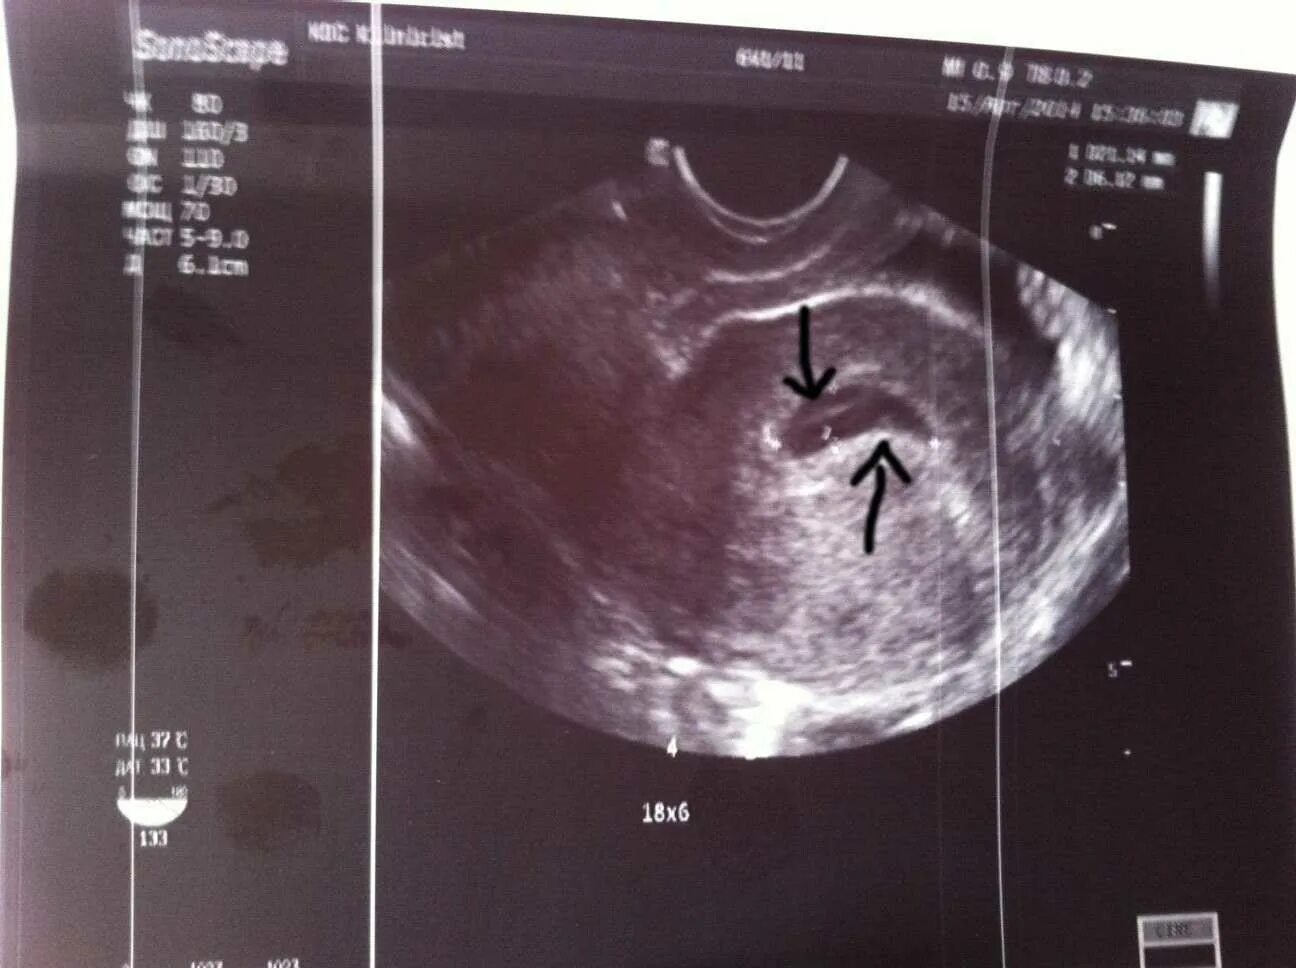

Увидят ли на 4 неделе беременность